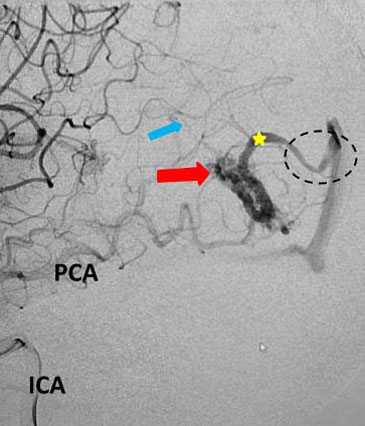

Fig 3. Lateral view, late-arterial phase of a right internal carotid artery (ICA) injection. Filling of the AMV (red arrow) by the fetal posterior cerebral artery (PCA) and small middle cerebral artery feeder (blue arrow). The large tortuous draining vein (yellow star) with venous stenosis and the suggestion of clot (dotted circle) can be seen.

The patient was taken to the angio-suite where an angiogram confirmed a high flow, high pressure AVM fed primarily by the posterior cerebral artery with a small collateral from the middle cerebral artery (Fig 2 and 3). The AVM drained into a tortuous, partially occluded and stenotic single draining vein.